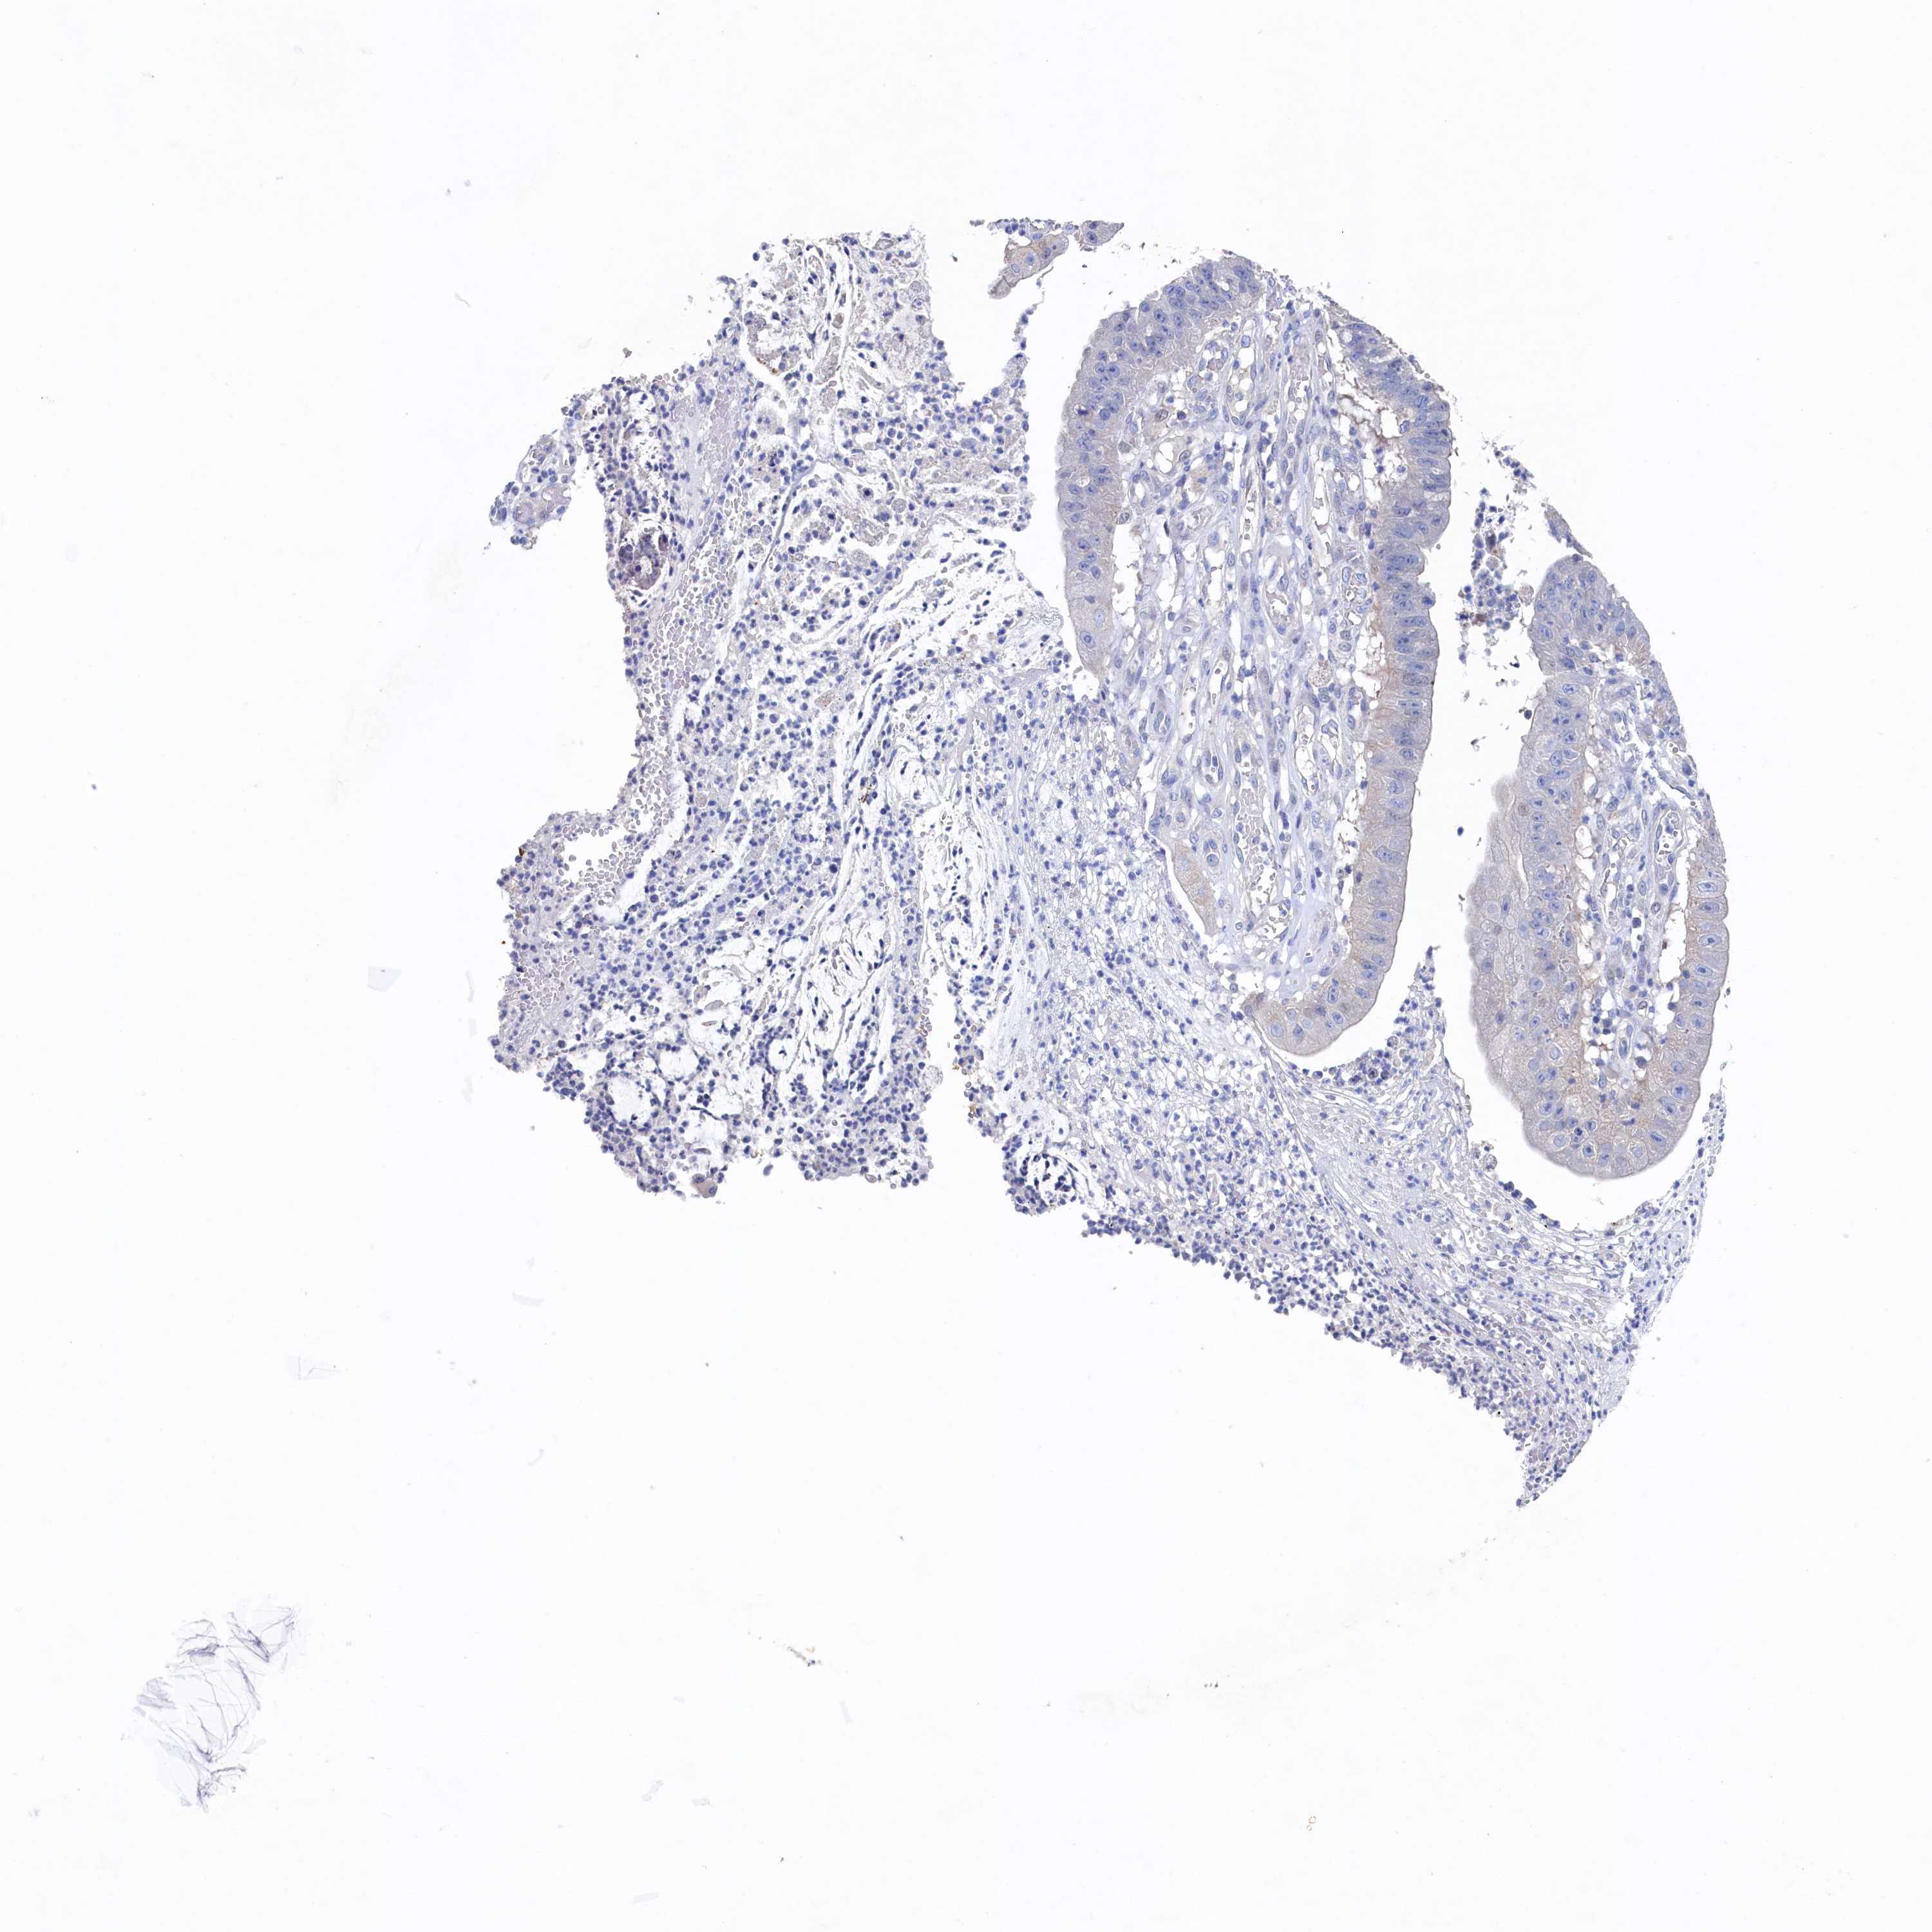

STOMACH CANCER - Protein expressioni

A mouse-over function shows sample information and annotation data. Click on an image to view it in a full screen mode. Samples can be filtered based on level of antibody staining by selecting one or several of the following categories: high, medium, low and not detected. The assay and annotation is described here.

Note that samples used for immunohistochemistry by the Human Protein Atlas do not correspond to samples in the TCGA dataset.

Antibody stainingi

Antibody staining in the annotated cell types in the current human tissue is reported as not detected, low, medium, or high, based on conventional immunohistochemistry profiling in selected tissues. This score is based on the combination of the staining intensity and fraction of stained cells.

Each image is clickable and will lead to virtual microscopy that enables deeper exploration of all samples and also displays staining intensity scores, fraction scores and subcellular localization as well as patient and tissue information for each sample.

Antibody HPA039908

Antibody HPA040774

Staining

High

Medium

Low

Not detected

Intensity

Strong

Moderate

Weak

Negative

Quantity

>75%

75%-25%

<25%

None

Location

Nuclear

Cytoplasmic/membranous

Cytoplasmic/membranous,nuclear

Adenocarcinoma, NOS

Adenocarcinoma, High grade